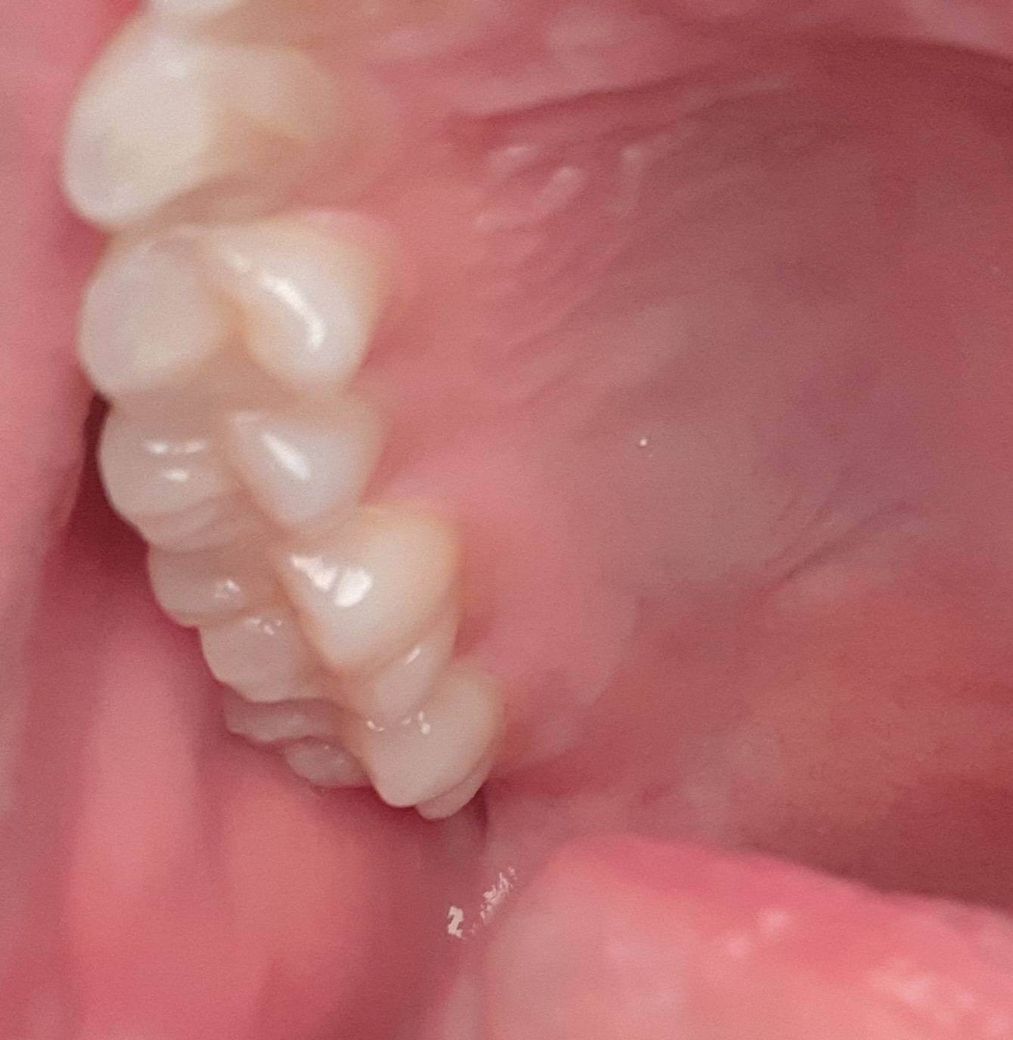

• 1번 째 사진

왼쪽 윗 어금니에 가끔식 통증이 와요.

처음 닿을때 살짝 시린느낌?신경이 아픈느낌? 이고 그다음부터는 닿아도 상관없는데 왜이러죠